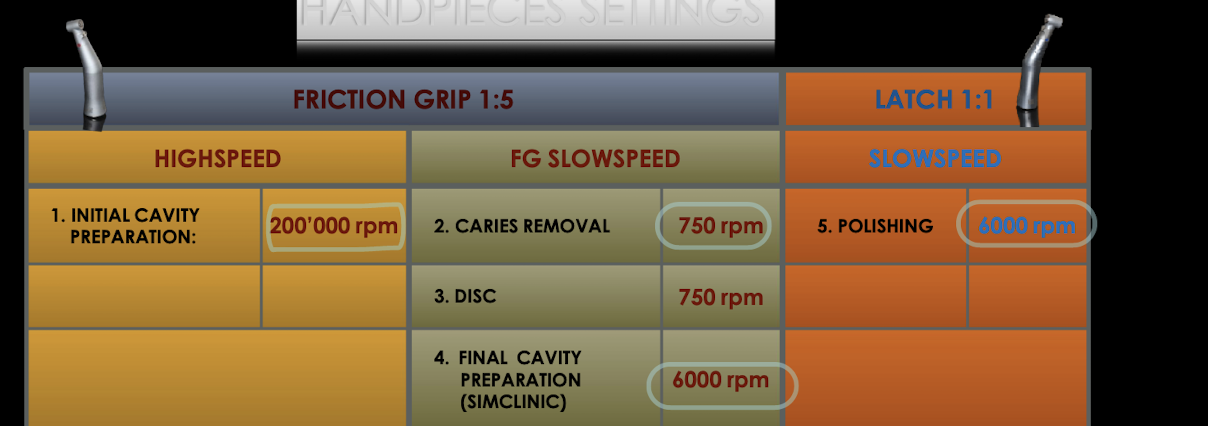

Gen principles of class V glass ionomer preps

All friable/weakened (unsupported) enamel should be ?

Do not extend to ?

When possible, preserve structure beyond ?

__ curves, no ?

Pulpal depth __ bulk for strength (__ mm from DEJ)

__ degrees cavosurface margin (no _)

bur should always be __ to surface you are cutting, and _ to enamel rods

Class V black’s prep:

__ shape

Class V - Blacks Prep

Internal Form

All external walls are __ to the external tooth structure, thereby _ the enamel rods

Extend the prep incisally, gingivally, mesially, and distally until all external walls are positioned in sound tooth structure at pulpal depths ranging from ___ mm at gingival wall to __ mm at incisal/occlusal wall

Axial wall

Depth of __ inside the DEJ

Follows the contour of the ?

__ mesio-distally, leaves dentin bulk for ?

Roughly __ to external tooth surface occluso-gingivally

orientation of walls

All four walls must meet the cavosurface at __ degrees

All walls will __ from axial wall to the cavosurface

Class V basics: outline form (sim lab) vs clinic

Extend to line angles, clinical extend to only enough to remove caries + unsupported enamel

class V GI prep:

Establish outline form:

Use a #____ or #___ bur for initial access and to develop __ internal line angles

Use a __L carbide bur to develop _ prep of walls

Extend to mesial and distal __ __

___, flowing __ (kidney bean shape)

Positioned __ mm supragingival, _ incisal/occlusal-gingival height (dependent on tooth)

Establish __ axial wall

Axial depth at ___ mm incisally/occlusally and __ mm gingival